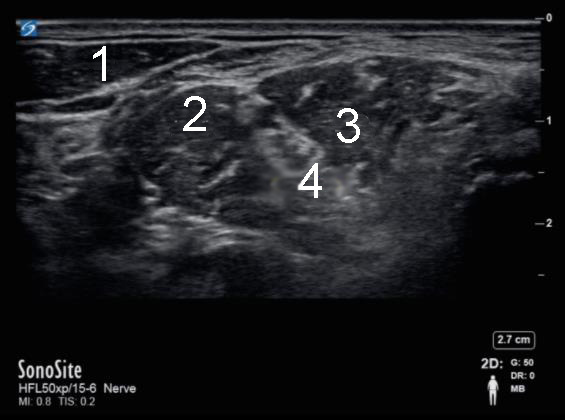

Interscalene Nerve Block - Pre-Injection Image

1. Sternocleidomastoid Muscle (SCM)

2. Anterior Scalene

3. Middle Scalene

4. Brachial Plexus